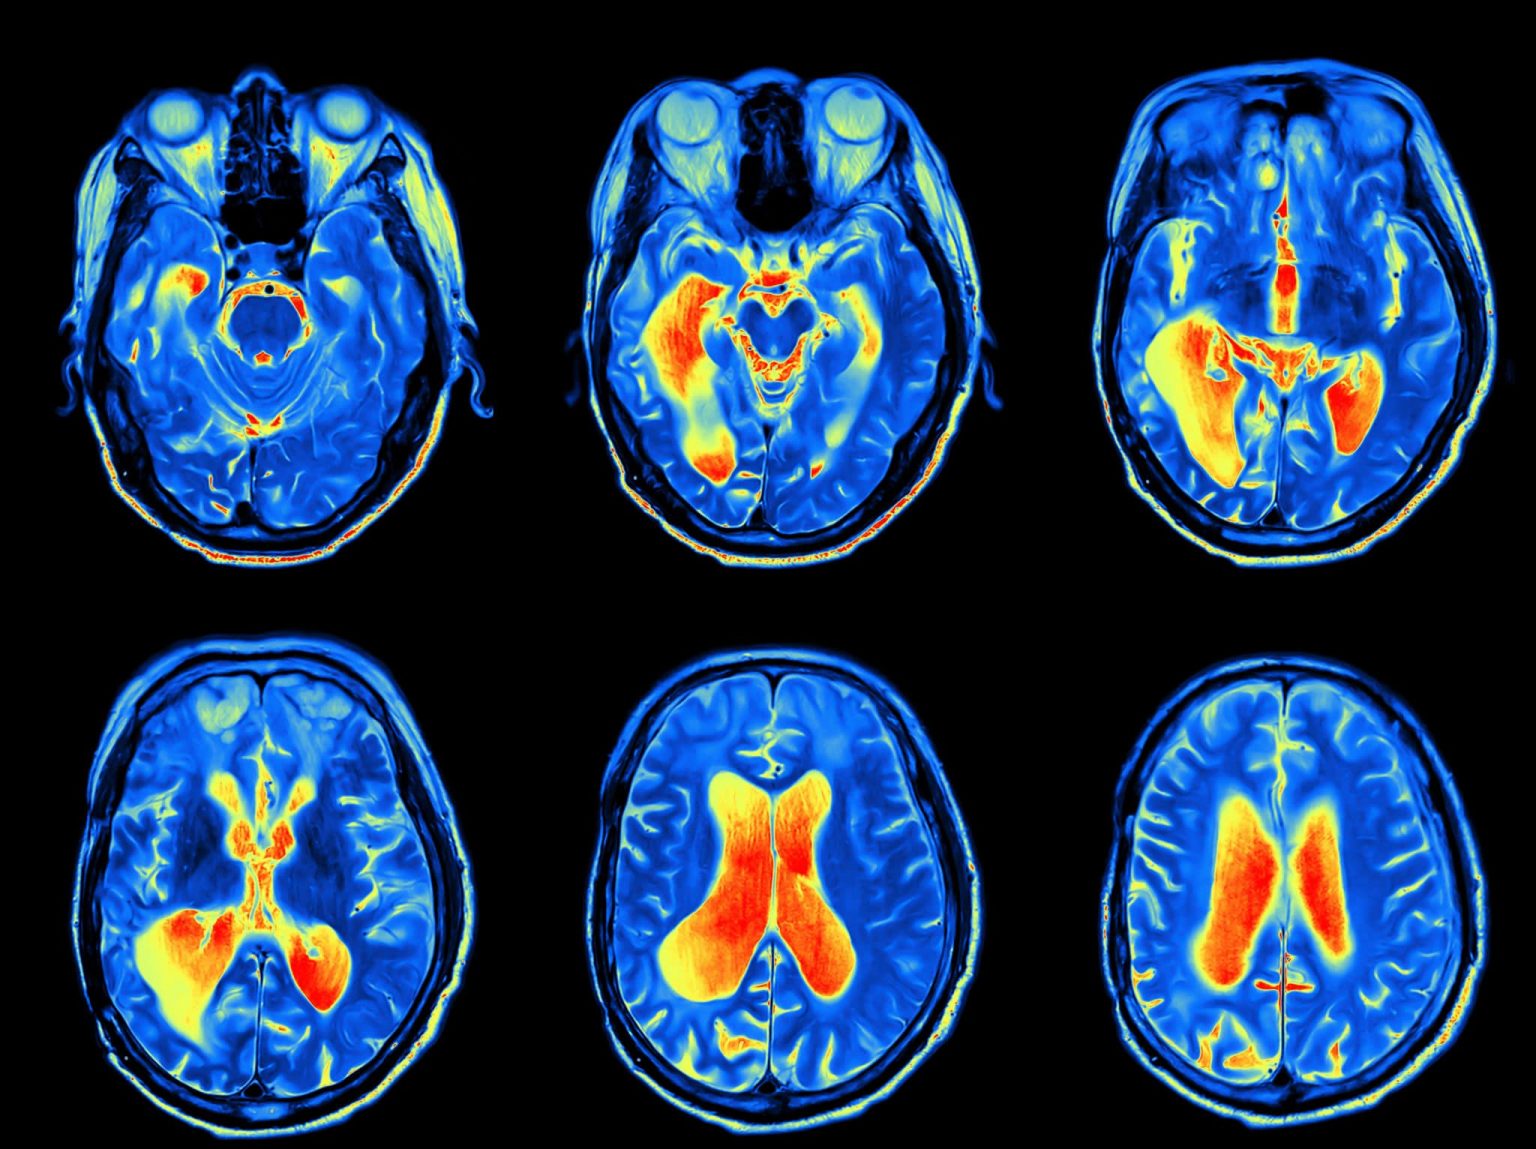

In order to diagnose tumors of the skull base, the physician will rely on a physical exam, a neurological exam and imaging studies. These might include CT scan, MRI, bone scan and positron emission tomography (PET) scan.